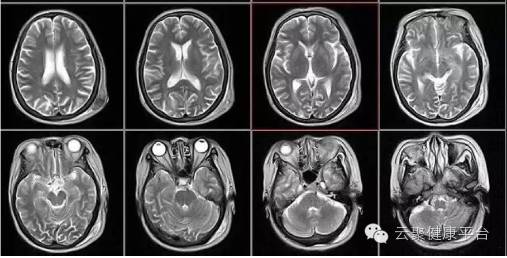

第五剑 核磁

核磁共振:核磁共振机使用较强大的磁场,使人体中所有氢质子磁场的磁力线方向一致,这时磁共振机的磁场突然变化,身体中水分子的磁力线方向,突然恢复到原来的状态。简单说就相当于用手摇一摇,让氢质子振动起来,再平静下来,感受一下里面的振动。所以,核磁共振也被戏说为是摇摇看的检查。

2、颈椎腰椎——最佳选核磁、次选CT

颈椎病、腰椎间盘突出等椎间盘疾病需要观察椎间盘与相应的神经根,要想更好观察这些软组织,最优选择就是核磁。同样,对于关节、肌肉、脂肪组织检查,核磁也是首选。